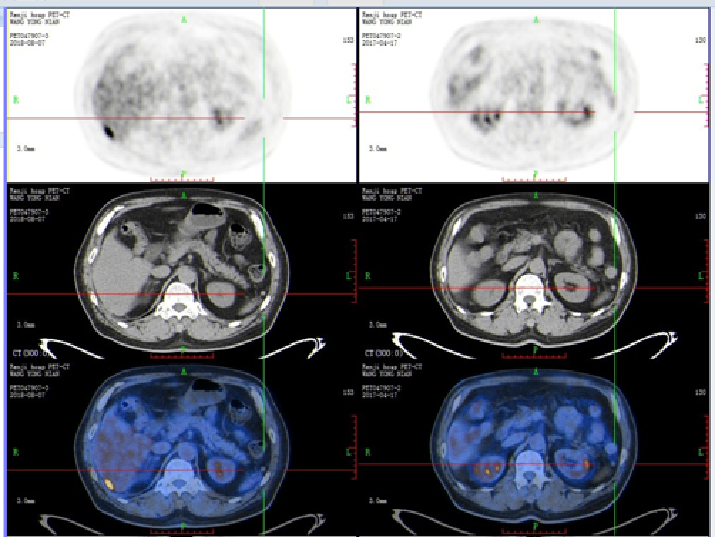

二线治疗:FOLFIRI+贝伐珠单抗

【贝伐珠单抗+FOLFIRI】2018-8-7 我院PET-CT提示直肠癌术后,吻合口FDG代谢未见异常,肝右叶转移瘤切除术后,脂肪肝,残余肝右后叶下段包膜下结节样FDG代谢异常增高(SUVmax 9.9),较前片新增,考虑肿瘤转移可能性大,双肺多发微小斑点、结节影,其中右肺上叶前段、后段两枚小结节(较大者直径约5mm,SUVmax 1.3)较前片新增,考虑为转移瘤可能。